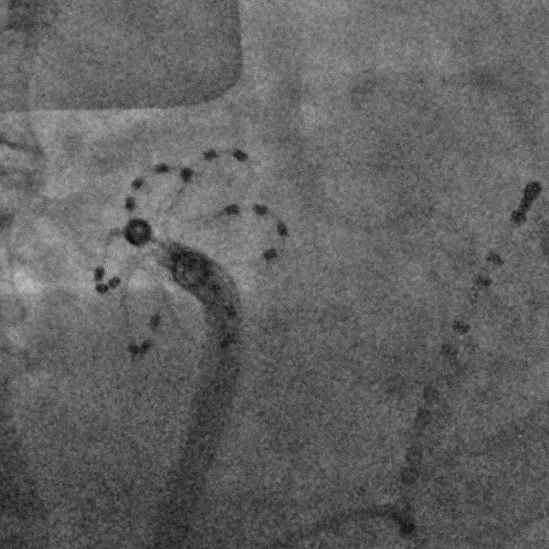

手术过程

手术在全麻下进行,消融策略涵盖双侧肺静脉、左房后壁及上腔静脉,总计消融73个位点,累计消融时间仅146秒。术中活化凝血时间(ACT)维持在250-300秒,未出现并发症。消融结束后,患者仍为房颤心律,经电复律成功转为窦性心律,手术顺利完成。

六瓣花导管呈网篮及花瓣形态放电

作为国内首个上市且拥有完全自主知识产权的花瓣状脉冲电场消融系统,CardiPulse®脉冲电场消融系统以其精准高效稳定安全的特点备受瞩目。采用One-shot消融技术,单次操作即可实现广范围隔离,操作简便且快速;优化能量参数实现肺静脉电位瞬时“秒杀”,显著提升手术效率;其螺旋镍钛骨架使得导管支撑可靠贴靠稳定,头端网格设计使得消融范围均匀,减少漏点风险;固定间距标测电极提供稳定信号,减少远场电位干扰,电位验证更准确。这些优势直指房颤消融中 “覆盖不全、信号干扰、操作繁琐” 等临床痛点。